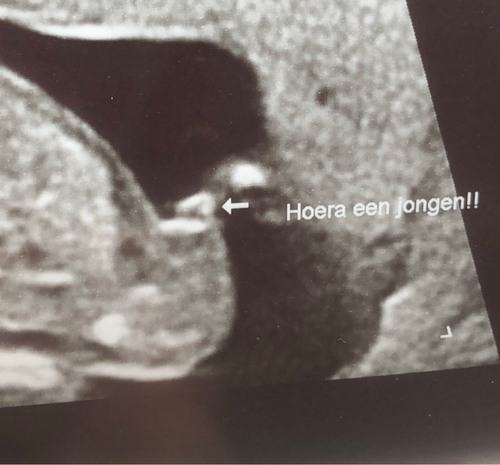

Bedankt voor je reactie! ❤️ mijn zoontje wil al steeds kusjes geven aan zijn broertje in de buik, dus dat komt helemaal goed. Ik heb geen traantje gelaten maar een beetje een gek verdrietig gevoel van binnen, van nooit een meisje, bij mijn partner trouwens hetzelfde die had een dochtertje ook leuk gevonden ondanks dat dit mannetje helemaal welkom is en we net zoveel van hem houden, 100% 💙